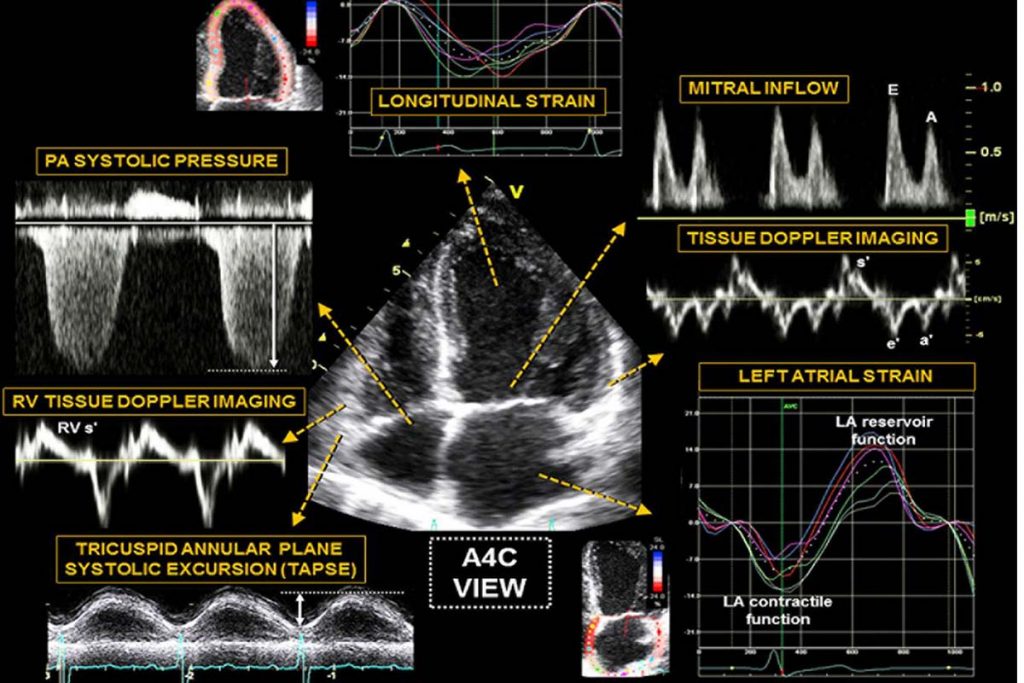

اکوکاردیوگرافی بافت داپلر چیست؟

سونوگرافی بافت داپلر شبیه یک آزمایش اکوکاردیوگرام است که در آن از امواج صوتی با فرکانس بسیار بالا استفاده می شود. در واقع در این تست این امواج فرکانس بالا را از قلب و رگ های خونی بیمار عبور می دهند. امواج صوتی برگشت دهنده (پژواک ها) توسط مبدل های مخصوصی جمع اوری می شود. این پژواک های جمع آوری شده به عکس هایی تبدیل می شوند که جریان خون را در سرخرگ ها یا قلب نشان می دهد.

قبل از پیشرفت تصویربرداری دو بعدی از قلب، اکوکاردیوگرافی بافت داپلر به عنوان یک روش غیرتهاجمی قلبی عروقی مورد استفاده قرار می گرفته است. تست اکو داپلر یک بخش جدایی ناپذیر از بررسی دقیق هموداینامیک قلبی است. هر دو عملکرد سیستولیک و دیاستولیک قلبی می توانند توسط اکوکاردیوگرافی بافت داپلر به وسیله اندازه گیری جریان خون مورد بررسی قرار بگیرند.